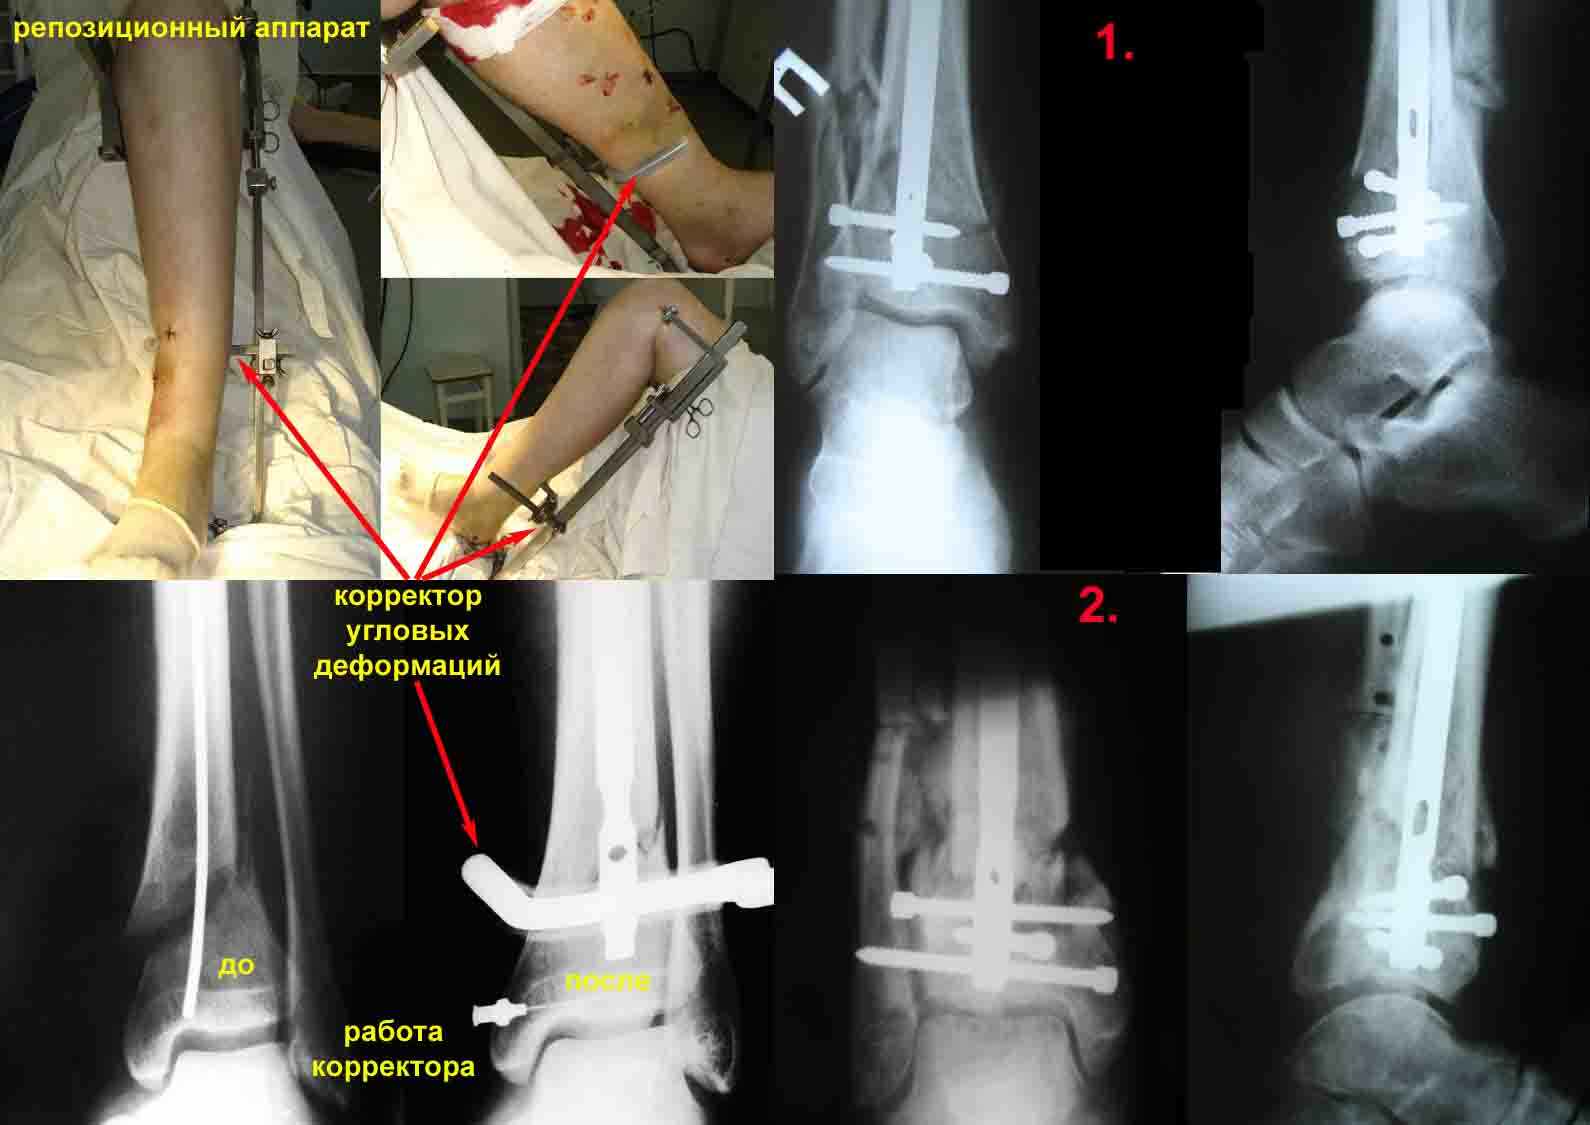

1. использование спицевого репозиционного аппарата для предварительной репозиция костных отломков на операционном столе и удержание костных отломков в репонированном положении на протяжении всего времени оперативного вмешательства.

Для примера – вложенный файл. Фотографии репозиционного аппарата и работа корректора угловых деформаций.

Механическое прицельное устройство для дистального блокирования предназначенное для проведения блокирующих винтов канюлированных стержней в разных плоскостях без ЭОПа (и вообще без применения рентгентехники) с успехом применяется нами, на протяжении вот уже десяти лет. (Рентгенограммы 1 и 2)